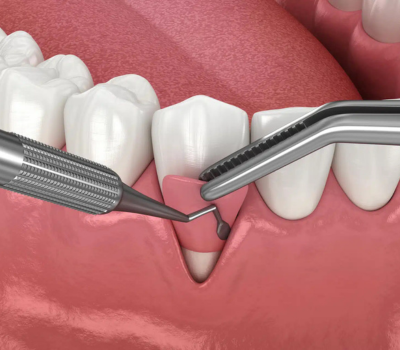

Tooth sensitivity occurs when the protective enamel wears down, exposing the underlying dentin and nerve endings. This can be caused by various factors, including:

If you’re struggling with sensitive teeth, relief is possible! Depending on the severity of your condition, we offer a range of treatments, including:

Some treatments, like fluoride therapy or desensitizing toothpaste, can provide relief in a few days, while others, such as dental bonding or gum grafting, offer long-term protection.